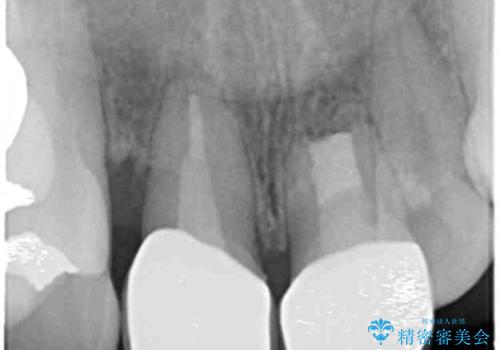

[ 重度歯周病 ] 骨造成・インプラント治療による咬合機能の回復

- 近医で重度の歯周病であることを指摘され、ほとんどの歯の抜歯が必要、入れ歯治療が妥当。と言われ、歯周病治療の相談を目的に来院されました。

歯周病の精密検査の結果、たくさんの歯が残すことが難しい状態でしたが、歯周病治療で歯を残すことができることと、骨の造成を行えばインプラント治療も可能である、と判断し入れ歯ではなく、しっかりと噛めるような治療ゴールを目指し、治療を開始します。